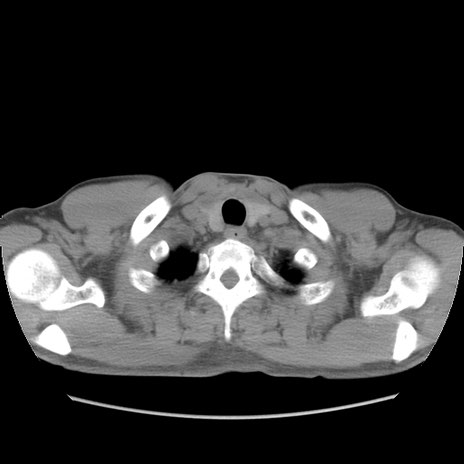

症例56 CT(横断像)

脂肪ウインドウ